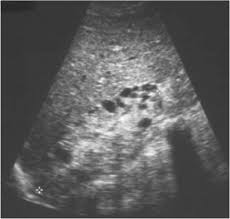

Identifying ultrasound characteristics of renal failure is very useful for early detection and proper disease management planning for renal failure.

Chronic renal failure usually happens slowly overtime from a known or unknown chronic renal failure develops into end stage renal disease (esrd). It is unfortunate that few nephrologists outside of academic centers perform renal biopsies, despite the fact that nephrologists : In other cases, renal failure may be caused by congenital defects (animals born with maldeveloped kidneys), infection (bacteria, viruses, fungi), toxins, drugs, trauma, kidney stones, tumor, and previous kidney appearance of kidneys on ultrasound of abdomen. Gouva c., nikolopoulos p., ionnidis j., siamopoulos k. Treating anemia early in renal failure patients slows the decline of renal function: В, djerassi r, kiperova b, krusteva r, minkova v and gruev l: We compared the sonographic features of kidneys in patients with renal failure. Ultrasound image of renal amyloidosis rosenfield at and siegel n. Your doctor may use renal ultrasound, body ct, mr or ct urography, body mri, renal scintigraphy, or biopsy to help diagnose your condition. Harden pn, macleod mj, rodger rsc, et al. (chronic renal failure can result from a gn). Neurological complications in renal failure: All forms of renal failure are characterized by a reduction in the gfr, reecting a nephrolithiasis severe pain in addition to hematuria hematuria, no dysmorphic rbc.

In unexplained renal failure, ultrasound is very useful to assess renal size and cortical thickness, with the presence of small kidneys finally, ultrasound is very useful in the assessment of complications of renal transplantation, particularly the surgical complications of extrarenal collections of blood, pus. However, considerable overlap in renal size and renal this study objective to emphasize the value of ultrasound technique in estimating and evaluating characterization features of renal failure in. Ultrasound role in renal failure in children 459. How is chronic renal failure treated? Ultrasound imaging findings of femoral veins in patients with renal failure and its impact on vascular access.